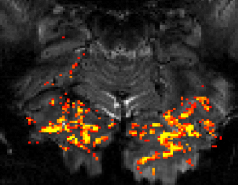

High-resolution functional MRI